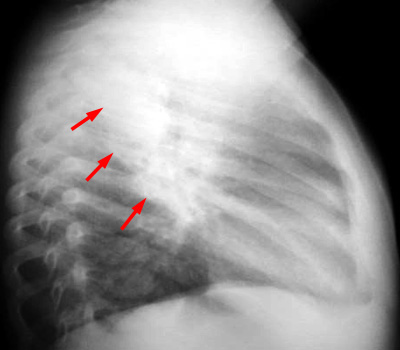

Primary TB produces a focal lobar consolidation in any pulmonary lobe. Hilar adenopathy and pleural effusions are common and should alert the radiologist to the possibility of TB.